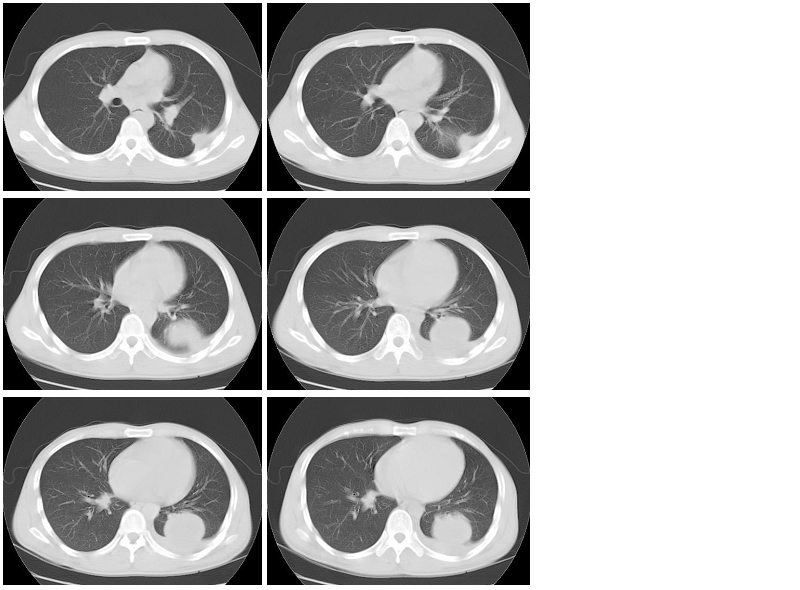

男性,34岁,咳嗽,胸痛一个月,左下肺呼吸音清。分别是肺窗(1-2),纵隔窗(3),增强动脉期(4),平衡期(5),平扫ct值为40-50hu,增强后厚壁达到80-100hu, [/color]

左肺下叶背段肿块影,边缘欠光整,无明显分叶,局部胸膜反应明显,增强扫描明显强化,其内见无强化低密度区,考虑左肺下叶化脓性感染,建议正规抗炎治疗后复查!鉴别诊断:1、结核瘤:环形强化或无强化,周围见卫星灶 2、周围型肺癌:分叶毛刺明显,局部胸膜凹陷征。

类圆形肿块,强化显著,内液化区无强化,考虑左下肺脓肿,左侧少量胸腔积液。